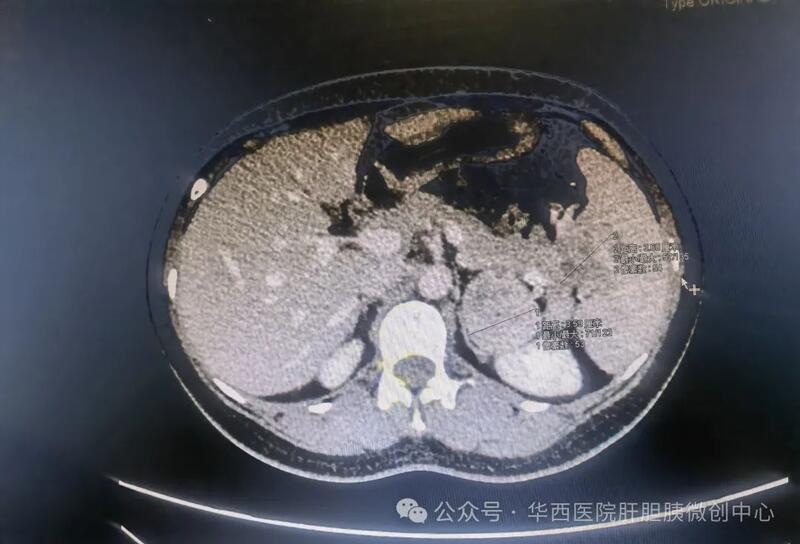

04 第四例:患者毛某,男,14岁,一年前在外院行阑尾切除术时发现 脾脏中段占位 ,后期随访发现脾脏实性占位逐渐增大,达到 5.9*5.0 cm,后经多方求医,最终在彭兵/李永彬教授团队成功实施了 首例腹腔镜下解剖性脾脏中段切除术 。手术不仅完整切除了肿瘤并且最大限度保留正常脾脏的体积和功能。

术前CT

完整切除中段肿瘤

该患者脾脏 占位较大且位于脾脏中段 ,仅保留脾上极或脾下极不足以满足最小剩余脾脏体积的要求(25%),但是考虑患者年仅14岁,为 未成年人 ,免疫系统发育不完全,全脾切除以后罹患肿瘤、感染、血栓形成等风险大大增加。

经反复讨论以及充分的术前评估,彭兵/李永彬教授团队决定为该患者实施腹腔镜下解剖性脾脏中段切除术,术中需要 完整切除脾脏中段肿瘤 并保留了 剩余脾脏动脉血供和静脉回流 ,以保证正常脾脏的体积和功能。患者术后恢复良好,于第7天顺利出院这也是我们团队实施的 首例 腹腔镜下解剖性脾脏中段切除术,且查阅了国内外文献,尚未发现相关的报道。该患者术后恢复良好,于第7天顺利出院。